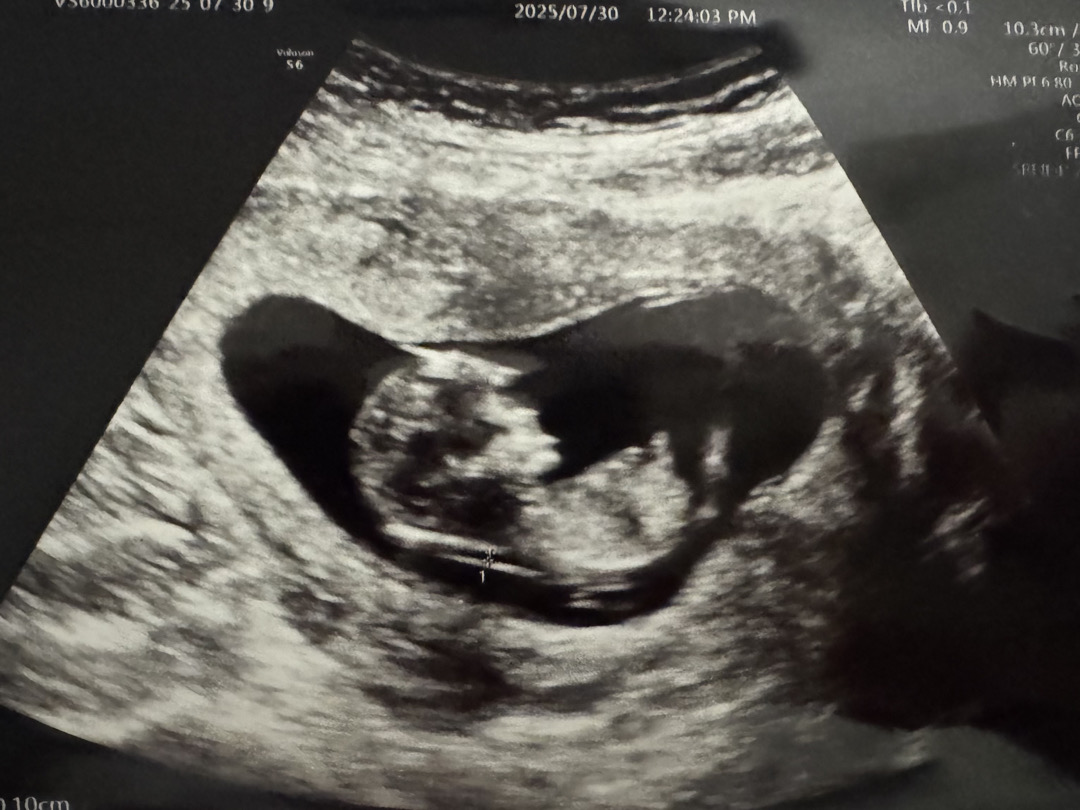

각도법 잘 보시는분 계신가용? ㅎㅎ

어떤 사진을 보면 딸각도같고 어떤 아들각도 같거든용.. 사진이 하나밖에 안올라가네요 ㅠㅠ 뭐가 탯줄인지 성기인지도 사실 모르겠고 ㅋㅋ 성별이 뭘까용??